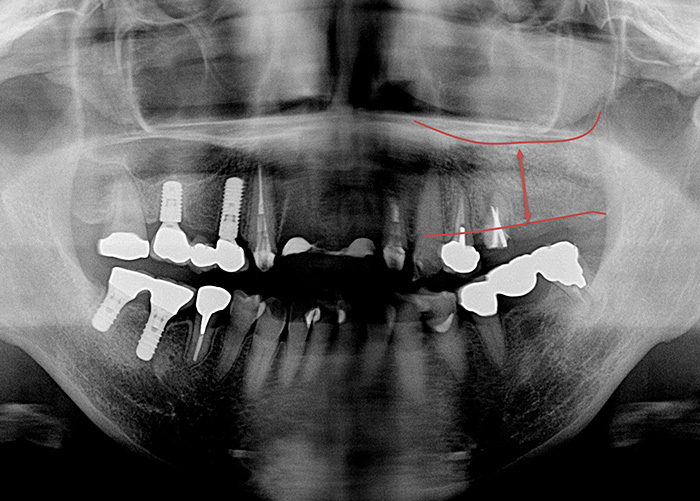

Case.09

![]() |

|---|

| 主訴 | 右上は骨が少ないのでインプラントができないと言われた |

|---|---|

| 治療期間 | 3ヵ月 |

| 治療費 | 50,000円(税込5,500円)(骨造成:サイナスリフト クレスタルアプローチ) |

| 治療内容 | 骨を増やす治療です。人工の骨を入れて不足した骨を増生します。 |

| 治療のリスク | 一時的な鼻出血、内出血、眼出血、上顎洞炎、腫脹のリスクがあります。 |